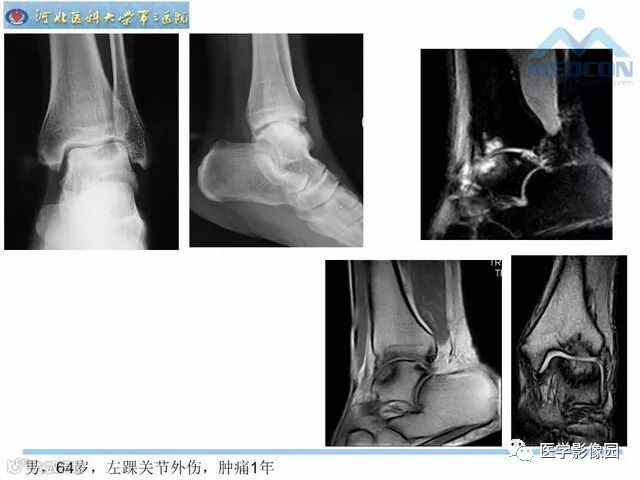

踝关节撞击综合征影像诊断,干货满满,值得收藏!

导读:踝关节撞击综合征影像诊断。干货满满,值得收藏!

踝关节撞击综合征影像诊断。干货满满,值得收藏!